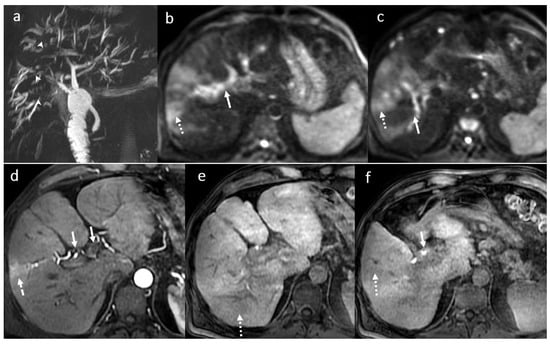

3.4. Biliary Anastomotic Stricture